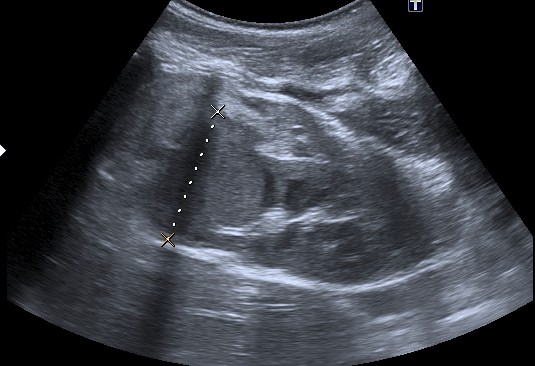

Ecografía:

- Masa renal bien definida e hiperecogénica de debido a la posible presencia de hemorragia, grasa, necrosis y raramente calcios.

- Las calcificaciones son raras. Su morfología es curvilínea (a diferencia del neuroblastoma = puntiforme).

- En ocasiones es posible diferenciar una pseudocapsula correspondiente a tejido renal sano comprimido.

- Es útil el Doppler para valorar afectación de la vena cava inferior por trombo tumoral.